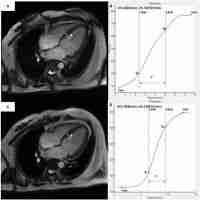

| Abstract | Non-invasive measures of the fetal ECG provide quantitative information on pacemaking rate, propagation times and velocities during normal sinus rhythm. One dimensional partial differential equation models of propagation that reproduce fetal normal sinus rhythm in hearts from 16-40 weeks gestational age were constructed Lengths were obtained from magnetic resonance imaging data, intercellular coupling informed by ECG timings, and cell excitation described by modified models for adult human cardiac cells. Spatially uniform progressive reduction of the L-type calcium conductance slowed the rate, and led to atrioventricular conduction blocks. Self terminating and persistent re-entry with a period of 240 - 300ms could be produced within a 1-D ring ventricular tissue model. The preliminary 1-D family of models quantitatively reproduces the observed timings of fECG intervals from 16-40 WGA, and predicts the characteristics of development of fetal A V block, and self terminating ventricular tachycardia. |